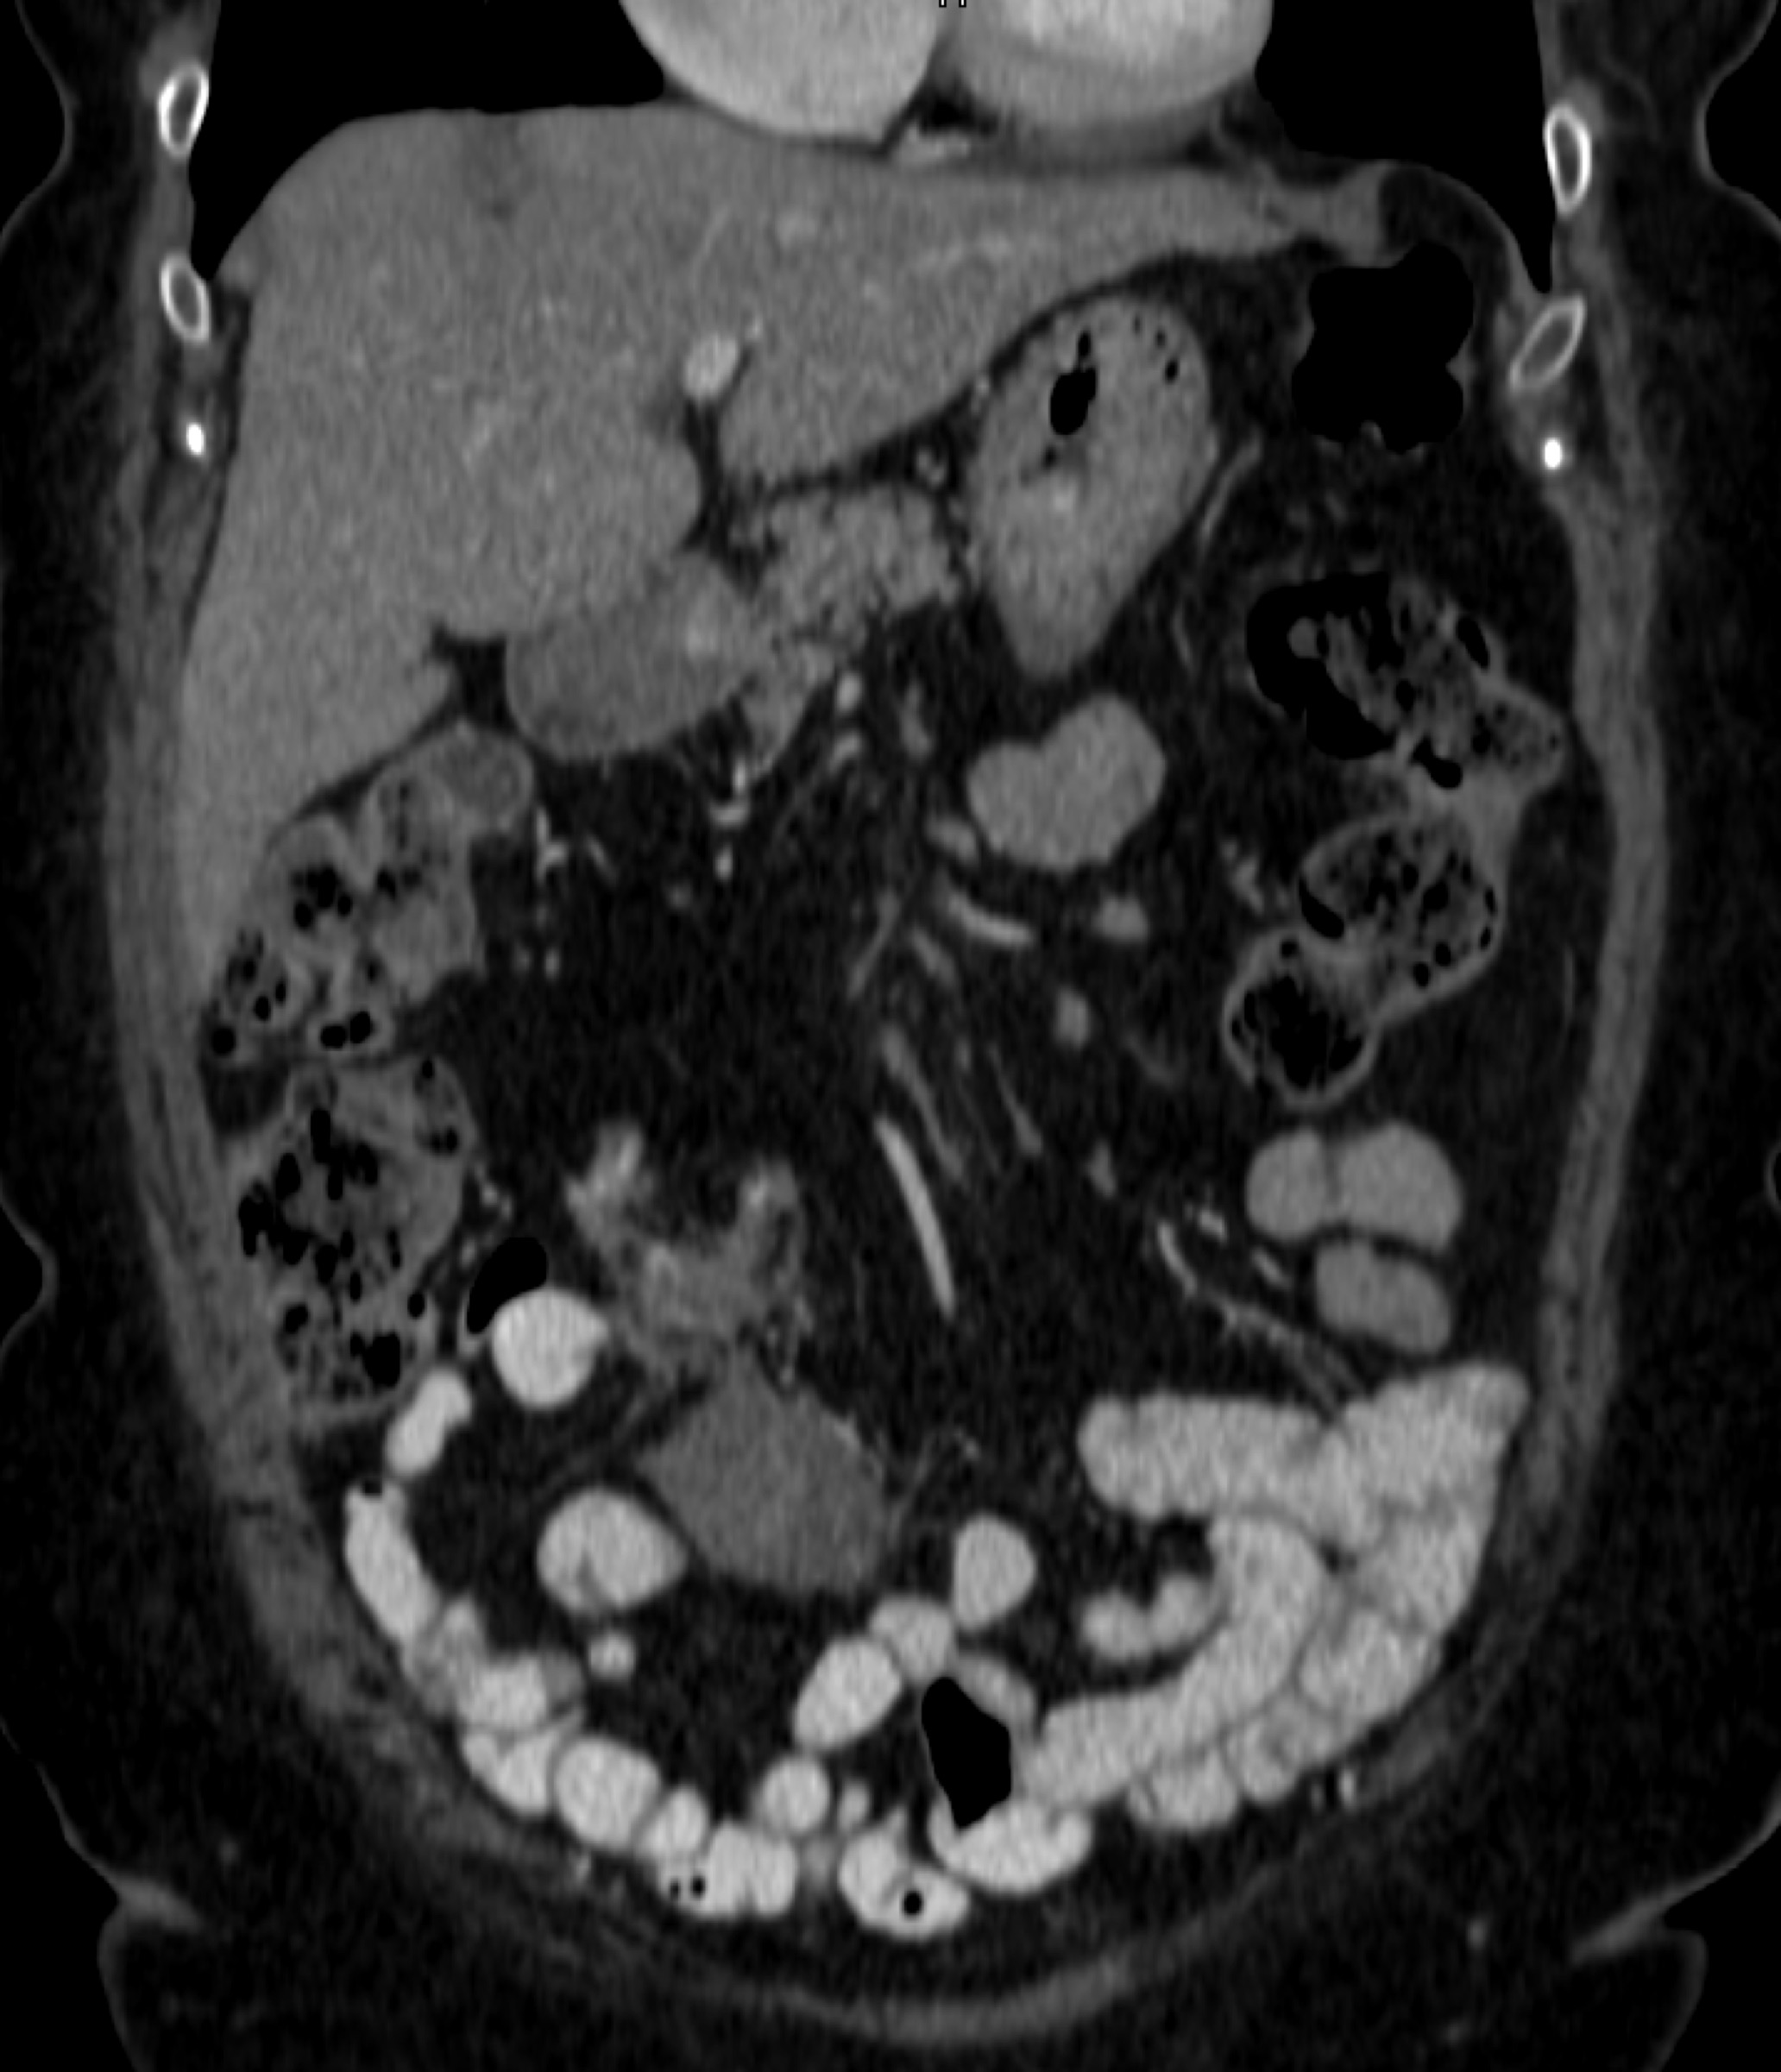

8) In this patient with RUQ pain and no history of trauma the best diagnosis is?

multiple hemangiomas

focal nodular hyperplasia

hepatic adenomas

angiosarcoma of the liver